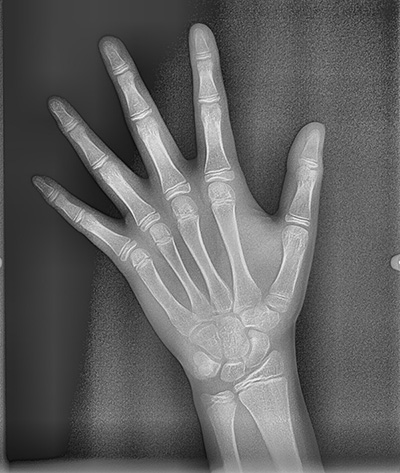

뷰노매드 본에이지 성장판 검사

아이들의 경우 추가적으로 성장판 검사도 진행하는데요. 뷰노매드 본에이지 검사는 손 엑스레이 사진을 판독하여 현재의 뼈나이와 예상 신장을 알려주는 검사입니다. 뷰노매드 본에이지는 약 72.5% 정도의 정확성을 갖는 검사로, 의사가 눈으로 판독했을 때보다 판독 일치도는 15% 이상 향상된 프로그램입니다.

요즘 진단을 해보면 어머님들께서 확실히 성장판 검사에 대한 관심이 아주 높더라구요. 아무래도 주변에 성장 주사를 맞는 아이들도 많다보니, 아이들의 키가 어느 정도까지 클지 많이들 궁금해하십니다. 손 엑스레이 사진을 촬영한 후 뷰노매드 본에이지 검사를 시행하여 예상 신장 결과를 정밀 진단때 설명해드리는데 어머님들의 만족도가 아주 높습니다 :) (저도 호기심에 제 아들 손사진을 찍어보았는데 예상키가 191.8cm가 나와서 깜짝 놀랐습니다 ㅎㅎㅎ)

뷰노매드 본에이지 검사 연세정원치과